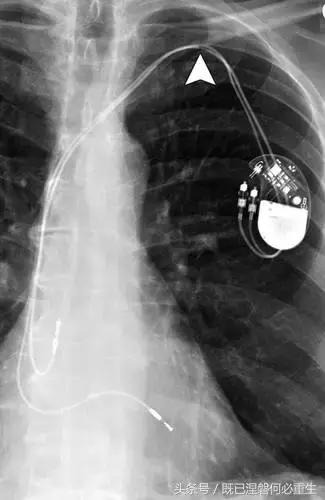

图5AB 在两个不同的患者电极错位和心室穿孔的例子。A,72岁的女性电极错误。 正位(A)和外侧(B)胸部X光片显示圣犹达医学双心室植入式心律转复除颤器与上腔静脉不适当的心房导线位置。 心房导联(箭头,A和B)的尖端高于右心房的水平,并且已经不适当地定位在上腔静脉中。 注意冠状窦引线(箭头B)的正常位置是在侧向投影中右心室(RV)引线的后方。

图5C,70岁女性心室穿孔。 正位胸片显示,圣犹达医疗双室起搏器的RV导联(箭头)超出心室轮廓。 心肌穿孔很少会导致放血或压塞。 患者没有受到并发症或随后的铅改变的不良影响(修订电极显示)。 心室穿孔可能导致对膜片的不适当刺激。